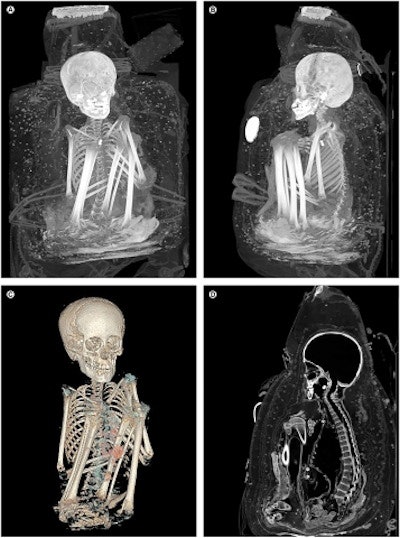

The last example concerns a packaged mummy with a so-called false head, from the Museum of Cultures in Basel. The checkered tunic is a typical garment of an officer of the Inca culture (1450-1533 A.D.). Radiocarbon dating of a fiber sample (A.D. 1480-1650) confirmed the era. A cut on the back of the tunic suggests that the mummy was manipulated by tomb robbers who dressed it in typical Inca clothing, perhaps to make it more attractive to buyers. A CT scan revealed that the boy, placed in a sitting position, was 7 to 9 years old. Traces of several diseases have been identified: A hereditary multiorgan disease (neurofibromatosis type 1) which caused changes in the skin and neural pathways. A parasitic infection such as Trypanosoma cruzi (Chagas disease) transmitted by bug bite is also suspected. Calcifications in the lungs indicate pneumonia or tuberculosis. Trauma to the chest and abdominal walls reveals a violent death. The reasons remain speculative.